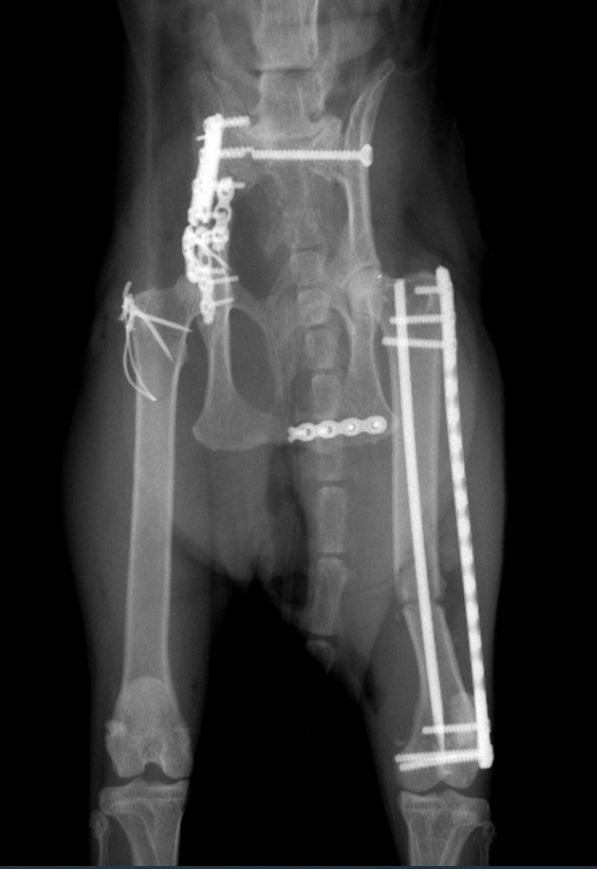

保護してそのまま近所の病院でレントゲンしたところ骨折7箇所でした。

骨盤脱臼、左右腸骨、尾てい骨、大腿骨関節付近、尾の7箇所骨折と内出血。

チタンプレートで固定する手術になります。

骨折治療箇所は6箇所(しっぽも骨折しておりましたがこちらは治療いたしません)

ほぼ同じような形になるので借りてきた画像で説明します。

このように腸骨の復元とチタンプレート固定で骨を正しい位置に修正します。

左脚の大腿骨遠位端成長板分離骨折

左側の腸骨骨折部の固定

両側の仙骨脱臼の整復

仙骨脱臼により骨盤が狭窄された形になり、重大な排便困難になる可能性が高いのでその治癒を目的とした治療です。

固定した腸骨の上端をボルトやワイヤーで内側に引っ張ることで仙骨を支点にして骨盤内腔を拡げます。